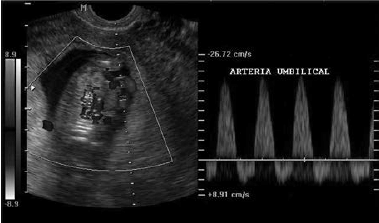

Considere a imagem a seguir:

Assinale a alternativa que indica corretamente o que a imagem representa e seu possível significado.